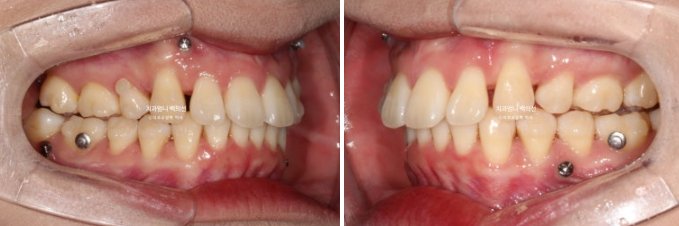

23.02-25.01

전 후 비교입니다.

총 치료기간은 1년 11개월이고 실제 장치를 낀 기간은 1년 9개월입니다.

윗니뻗침이 심하면 아랫입술이 윗니 뒤에 걸려 입을 다물었을 때 윗니 끝단이 살짝 보입니다.

입술이 편하게 안 다물리는 상태이고 이를 입술부전증 이라고 합니다.

발치교정에서 많이 걱정하시는 부분이 팔자주름, 인중 길어짐, 입술 말려들어감 등입니다.

이런게 보이지 않습니다.

돌출감도 해소가 되었고 입술 볼륨도 잘 유지가 되었습니다.

발치교정 부작용 합죽한 입매 요즘 누구도 좋아하지 않죠

이런 부작용은 치료계획 단계부터 고려해야합니다.

개선된 앞니 각도가 돋보이고 깔끔한 인상을 줍니다.

잘 유지된 스마일라인과 적절한 입동굴은 미소 심미에서 중요한 부분입니다.